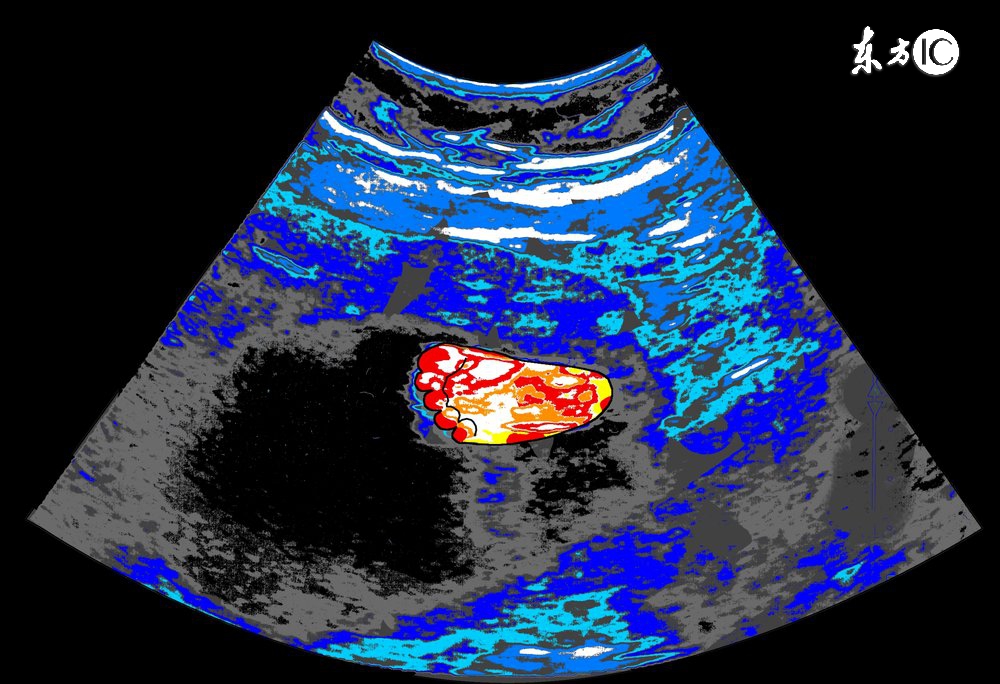

孕中期(4-6个月)

1、检查的目的:

确定胎儿大小是否与实际孕周相符,确定胎盘位置,视察羊水量,视察胎儿有无明显畸形及脏器发育状况。

2、胎儿大小:

通过测定胎头的双顶径、头围、腹围及胎儿股骨的长度来判断胎儿的生长发育情况。

3、胎盘位置:

正常胎盘附着于子宫的前壁、后壁、宫底或侧壁,如果B超显示胎盘在子宫下段,甚至胎盘下缘达到或覆盖宫颈内口处,即为前置胎盘,前置胎盘属于高危妊娠的一种,并随着怀孕月份的增大,容易发生无痛性阴道出血,引起流产或早产。

4、羊水量:

羊水量对胎儿的生长发育十分重要,羊水过多或过少,都可能预示着胎儿畸形,一般B超单上用羊水指数来表示羊水量的多少,用以评定胎宝宝的生长发育情况,正常范围值是5-18厘米。

5、脏器发育:

孕中期的B超检查,能够清晰的视察到胎宝宝的脏器发育情况,包括面部神经系统、消化系统、泌尿系统等,可以及时发现胎儿畸形,如胎儿的肢体畸形、唇腭裂畸形等,孕妈妈还须关注B超单上的胎儿脊柱检测栏,如标注为连续,则代表正常,缺损为异常提示,可能脊柱有畸形的情况。